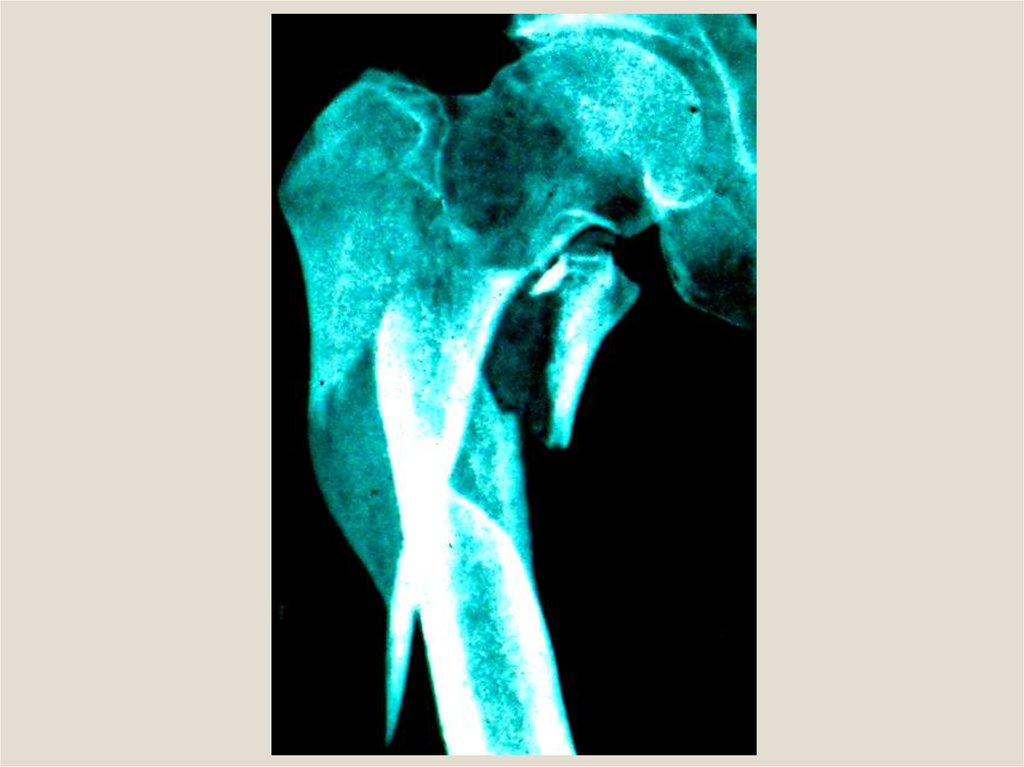

Клиническая анатомия смещения отломков при переломах трубчатых костей. Остеотомия, остеосинтез, пластика трубчатых костей